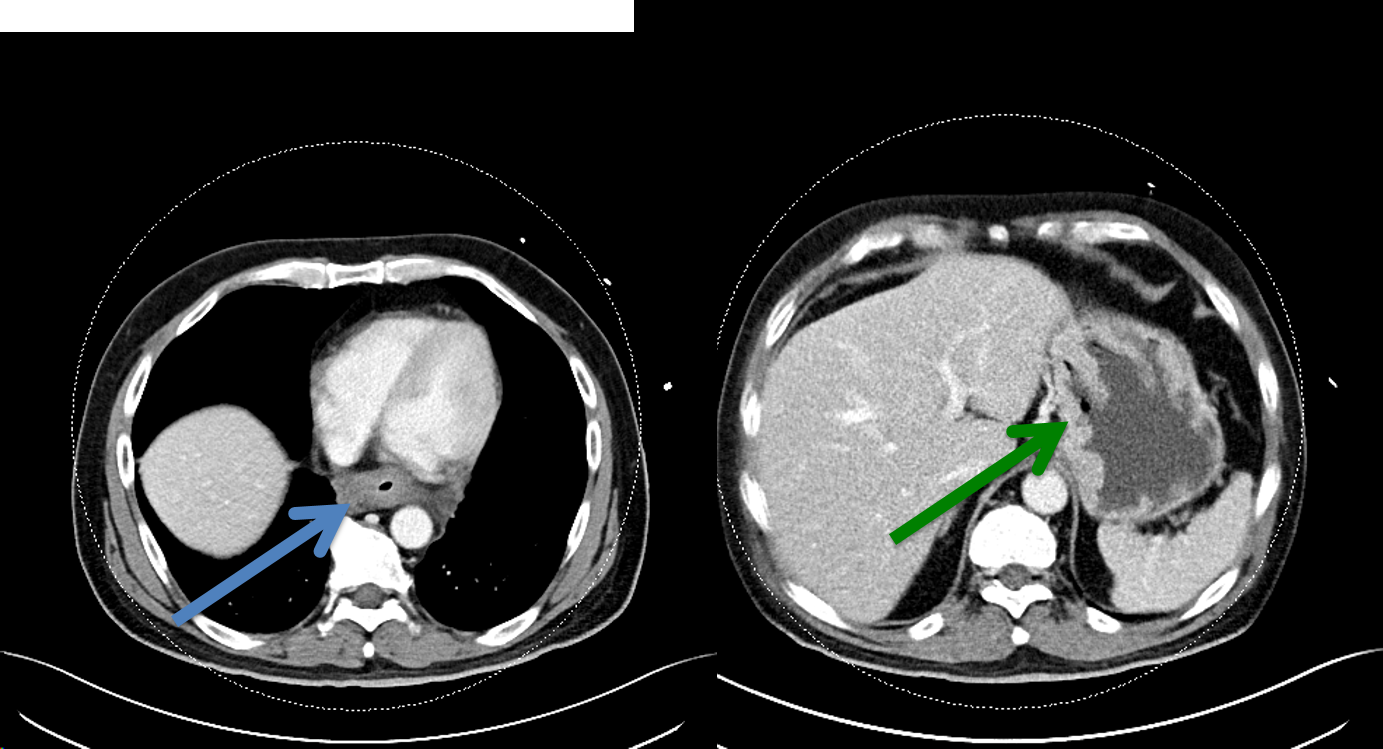

These highly vascular tumors classically show enhancement on arterial phase.

Neuroendocrine tumor is in the differential for hypervascular liver metastasis. Remember the mnemonic “CT/MRI”.

Choriocarcinoma, thyroid cancer, melanoma, renal cell carcinoma, and islet cell tumor (neuroendocrine tumor)